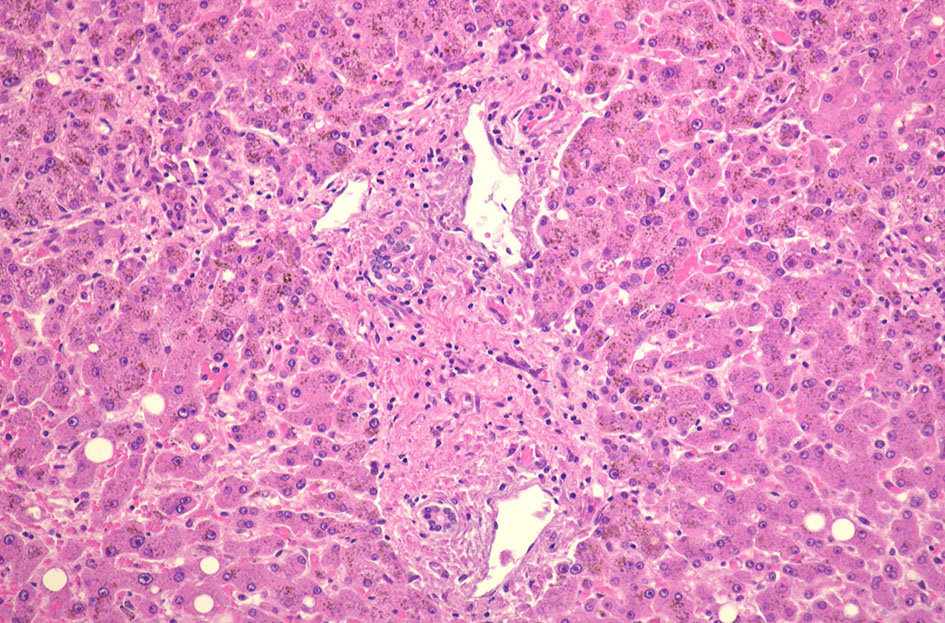

IWT症例 70歳代男性 3年前より胸部不快感, 体重減少。大球性正色素性貧血を指摘される。

70歳代男性の骨髄。hypercellular marrow. M/E=1-2, erythropoietic hyperplasiaを認める(1, 2). megaloblastosisが出現。(3).

Mgkは成熟大型のものが多い(4). 単核, 小型球状核のMgkも認められる(5)

骨髄ブロック, スメアの鉄染色

骨髄塗抹標本と組織(clot section)の鉄染色(クリックで大きな画像がみられます) ring sideroblastは鉄顆粒が核周囲にまとわりつくように見える赤芽球として認められる。Hb合成の乏しい幼若な大型赤芽球では認められる鉄顆粒は少ない。

骨髄ブロック免疫染色 RARSとRCMD-RS, high-grade MDSとの鑑別に, CD34, p53, CD42b免疫染色が役に立つことがある